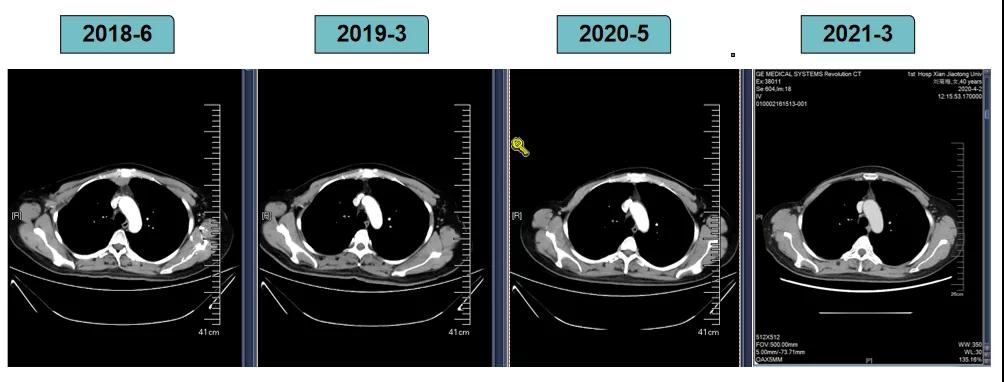

影像学评估-纵膈淋巴结:

2018-7-17成功入组ELAINA临床研究(试验方案编号:BO29919),IWRS分配随机号3210。于2018-7-17开始接受T-DM1 3.6mg/kg(252mg)治疗,并间断对其进行疗效评估。现阶段患者PFS达近40个月。

靶病灶:腹主动脉左侧和下腔静脉右侧淋巴结

非靶病灶:肝左叶、肝右前叶下段;纵膈胸骨后淋巴结节;前上纵膈淋巴结;腹膜后小淋巴结